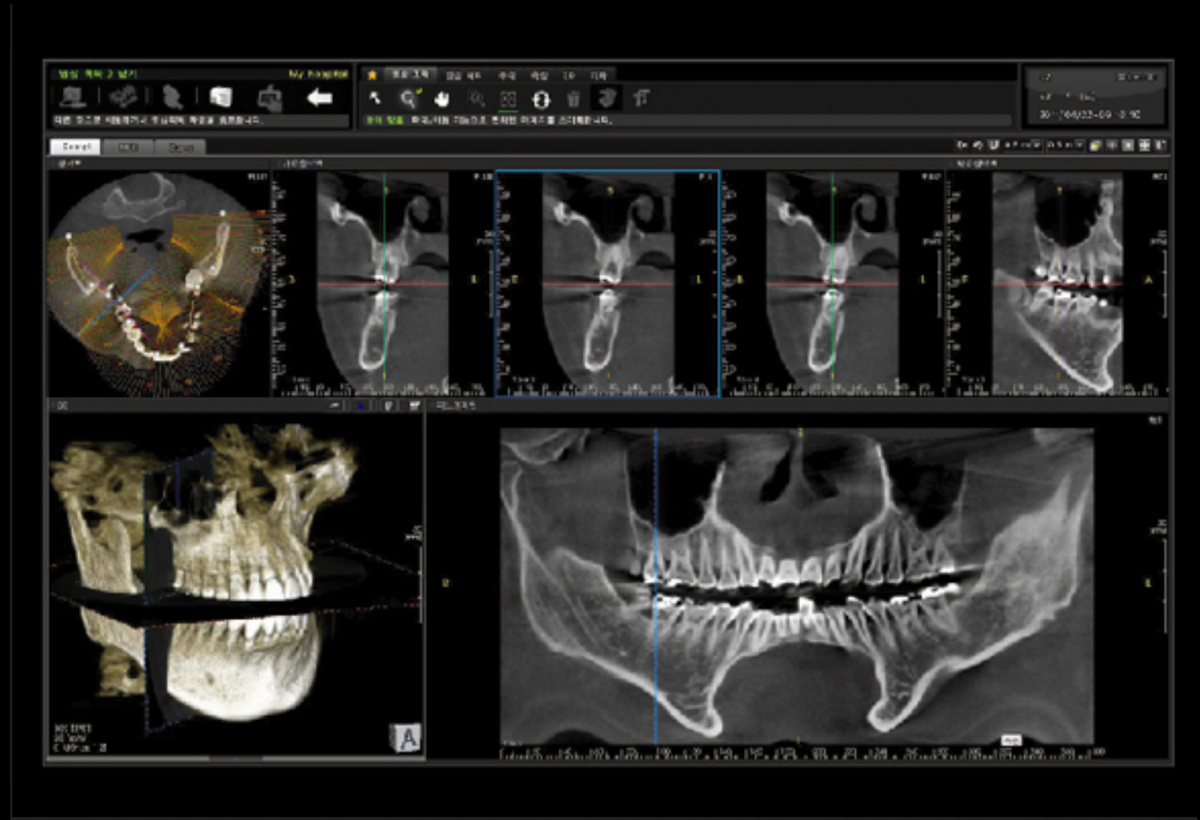

Немаловажным, а может главным вопросом, является универсальность программы-просмотровщика, в которой будут работать врачи-стоматологи. У Papaya 3D есть два варианта программ: Triana и OnDemand3D. Оба просмотровщика обладают схожим интерфейсом и имеют самые важные опции, а именно:

Таким образом обе программы являются простыми в пользовании, но обладающими обширным спектром возможностей для диагностики любыми специалистами-стоматологами. В данные программы происходит загрузка классических файлов DICOM 3.0, которые являются общепринятым форматом записи данных пациента. Это важный момент, так как позволяют врачу, имеющему полную версию программы загружать даже сторонние исследования и просматривать их в этих программах. Простота в освоении этих программ позволяет даже специалисту, не работающему раннее с этими программами, быстро адаптироваться и получить качественную информацию. Возможность выгрузки STL-файла дополнительно создает возможность интегрировать данные с цифровым ортопедическим протоколом.